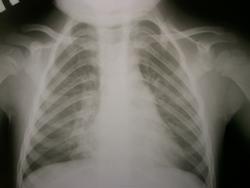

Первые 2 снимка сегодня, вторые 2 майские.

Написал бы р-признаки ателектаза средней доли правого легкого. Если есть возможность, сделал бы снимки по Флейшнеру.

Не знаю, есть ли смысл делать по Флейшнеру, гипопневматизация и так видна хорошо. Разве только ради красивой картинки. А вот фтизиатру показать ребенка надо. Изменения идут еще с мая. Некрасивый корень правого легкого, очень вероятно увеличение л/у.

Сейчас ателектаз средней доли. Плюсую к бронхоскопии.